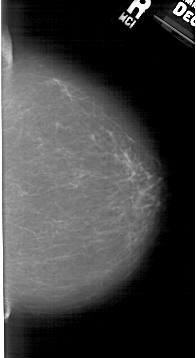

A_1942_1.LEFT_CC

RIGHT_CC LINES 5011 PIXELS_PER_LINE 2731 BITS_PER_PIXEL 12 RESOLUTION 43.5 NON_OVERLAY